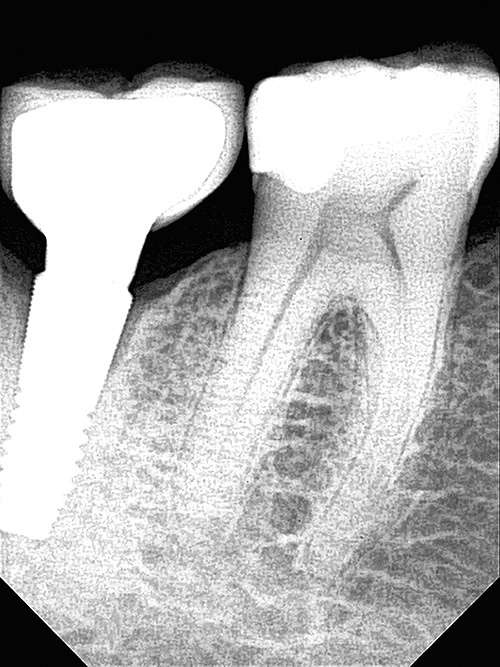

OPTEO Sensor – Klinische Bildgalerie

Ultra-HD Bildqualität – 18,5 Mikron Präzision Außergewöhnlich klare und detaillierte intraorale Bildgebung.

Ein hochwertiger dentaler intraoraler Sensor

Ultra-HD-Bildqualität für perfekte Zahnfilme.

18,5 Mikron Auflösung.